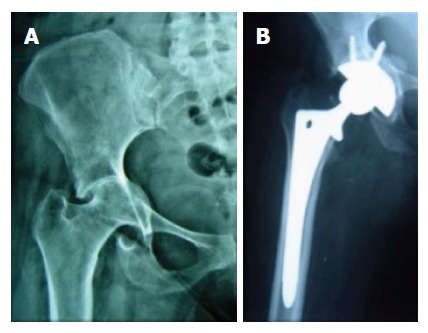

Twenty-five patients had acetabular protrusion (Type I and II Paprosky defect) for which impaction grafting from the femoral head was done was done (Figure 1). The bone grafts consolidated in all the patients at 3 mo. The mean Harris Hip Score improved from 27 (range, 20-36) to 91 (range, 88-94) at the latest follow up. The improvement in Harris Score was similar in both males and females.

Figure 1.

Preoperative X-rays of a patient suffering from Post-tubercular arthritis of hip with protrusion (A) and post-operative X-rays following a cementless total hip replacement along with autogenous impaction grafting for protrusion hip (B).